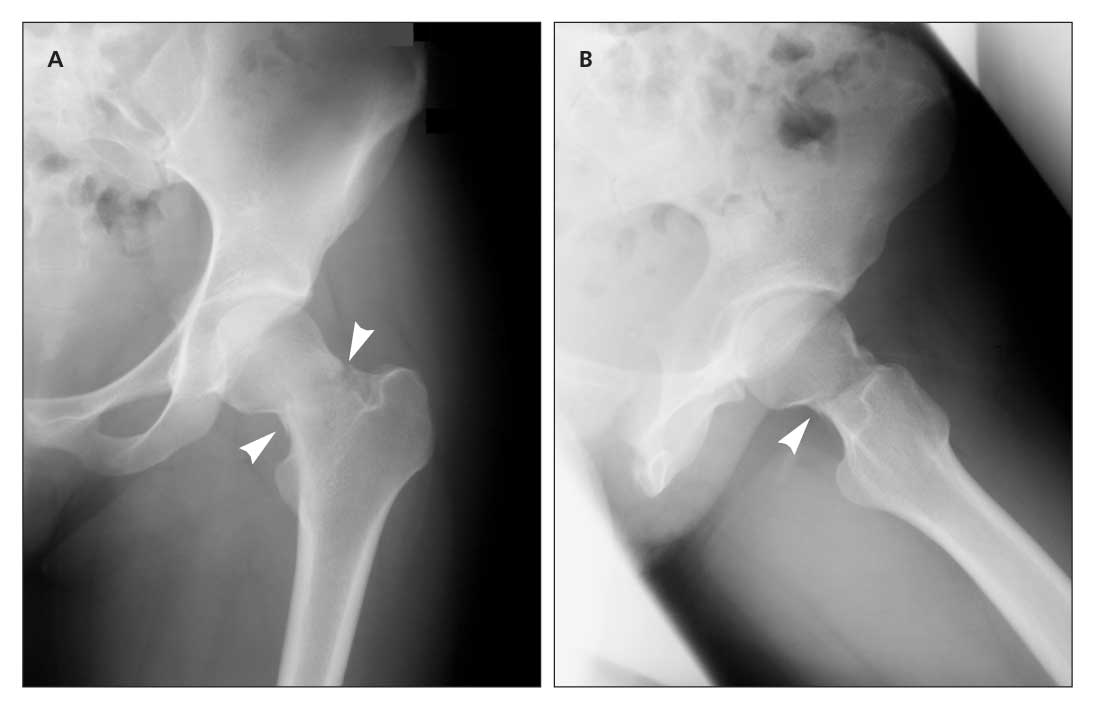

Femoral Stress Fractures